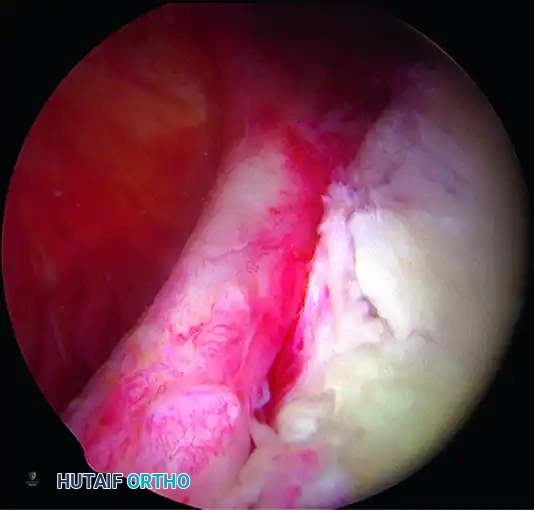

A, Soft tissue Bankart lesion.

1. Capsulolabral Mobilization and Glenoid Preparation

While visualizing from the anterosuperior portal, use an arthroscopic elevator or radiofrequency wand to meticulously free the capsule down to the 6-o’clock position. You must release the tissue until the underlying red muscle belly of the subscapularis is clearly visible. This complete release is mandatory to allow the inferior capsule to be shifted superiorly without tension.

💡 CLINICAL PEARL: The Biological Bed

Soft tissue healing requires a robust vascular response. Use an arthroscopic rasp or motorized burr to abrade the anterior glenoid neck down to bleeding cancellous bone. Do not over-resect the bone, as preserving the cortical edge is necessary for secure anchor purchase.

A, Abrasion of glenoid neck and capsular release to allow advancement of capsulolabral complex superiorly and laterally to restore anatomy and physiological tension.